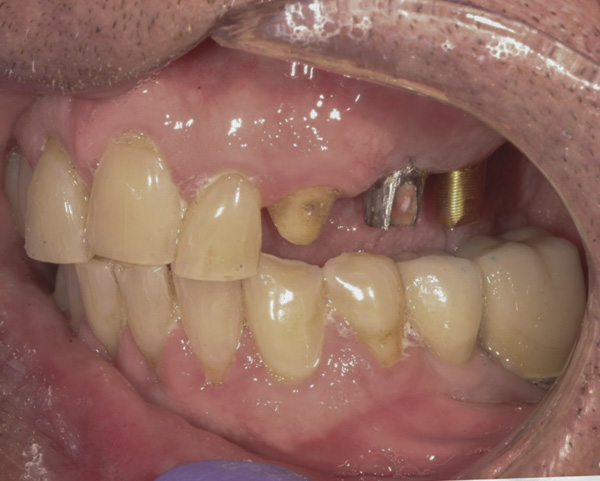

Case 6 – Root Submergence

Background: This patient presented with a failing maxillary bridge spanning teeth Nos. 6 through 11. In order to keep the patient in a fixed transitional prosthesis, the first phase of treatment involved placing a provisional restoration on Nos. 6 through 11, with the first set of implants placed at sites Nos. 6 and 11. Once implants Nos. 6 and 11 integrated, custom abutments were placed, and the provisional was relined to add their support. Then implants and their respective subsequent abutments could be placed at positions Nos. 7 and 9 (Figure 20). Tooth No. 8 received elective endodontic treatment in order to be reduced and eventually submerged following insertion of the abutments at Nos. 7 and 9 (Figure 21 and Figure 22).

Results: In Figure 22, it is apparent that there is no recession around abutments Nos. 7 and 9 following root submergence. Of additional note, Figure 23 illustrates excellent bone labial to all the implants, with no recession around abutments Nos. 6 or 11. These first abutments were inserted 8 months prior to the ones at Nos. 7 and 9. The time between Figure 21, when root submergence took place, and Figure 23, when the final bridge was to be inserted, was 7 months. Figure 24 shows placement of the provisional bridge on all abutments.

Figure 20 Implants and their respective subsequent abutments placed at Nos. 7 and 9.

Figure 20

Figure 21 Endodontically treated tooth No. 8.

Figure 21

Figure 22 Tooth No. 8 eventually submerged following abutment insertion at Nos. 7 and 9.

Figure 22

Figure 23 Excellent bone labial to all the implants; no recession around abutments Nos. 6 or 11.

Figure 23

Figure 24 Provisional bridge on all abutments.

Figure 24